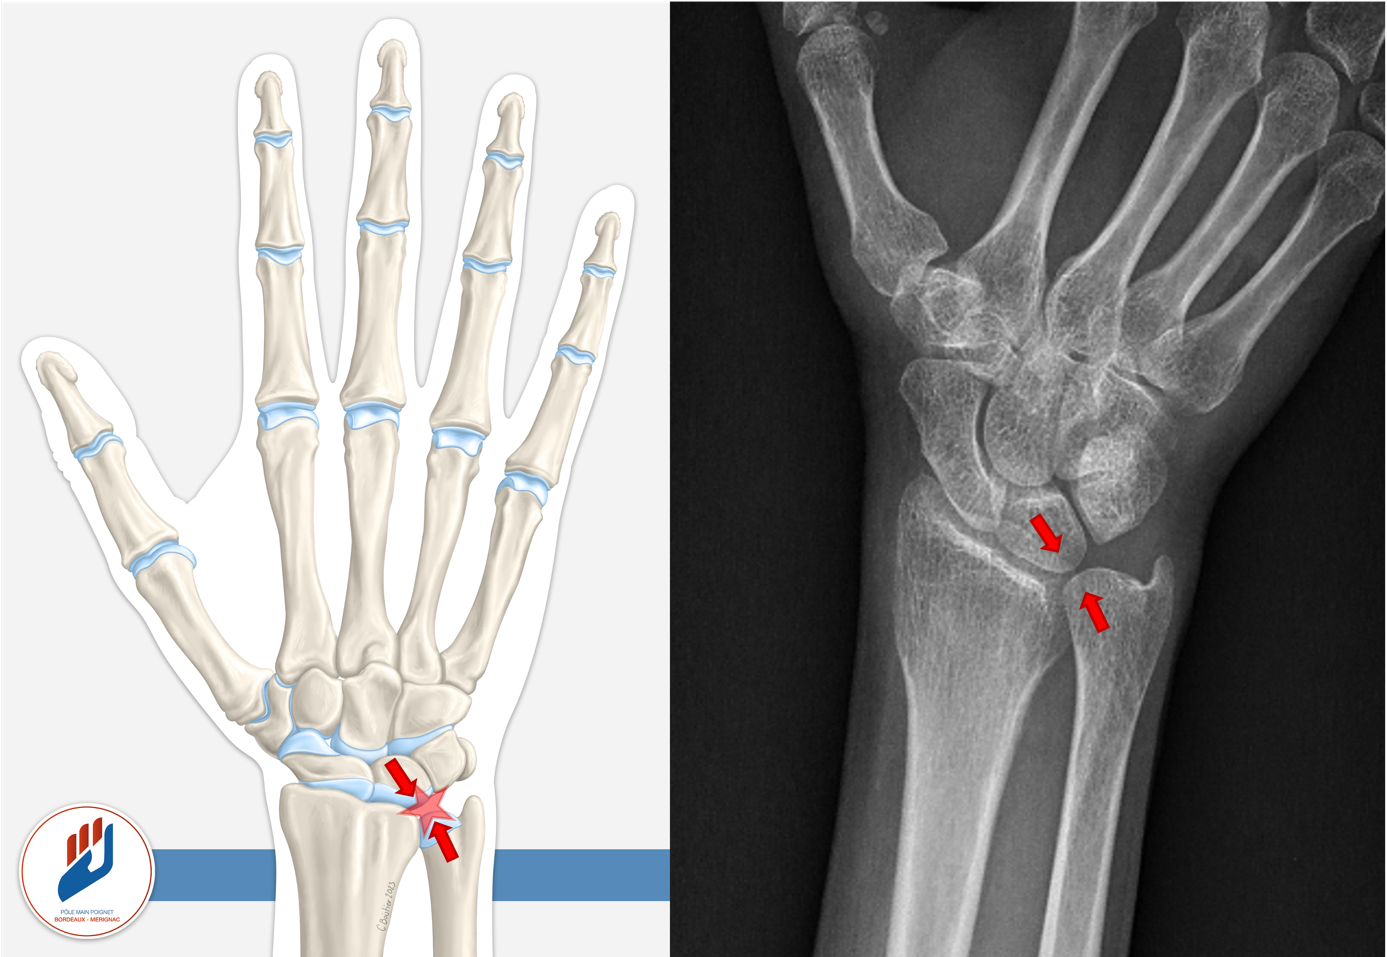

Le conflit ulno carpien correspond à un contact excessif entre l’extrémité distale du cubitus (l’os de l’avant-bras situé du côté du petit doigt) et les os du carpe et notamment le lunatum. Ce frottement anormal use progressivement le fibrocartilage du ligament triangulaire (TFCC), une structure clé de l’articulation, et peut entraîner une usure du cartillage du lunatum, des lésions ligamentaires (luno triquétrale), une inflammation chronique, voire une arthrose à long terme.

Ce phénomène est particulièrement fréquent lorsque le cubitus (en bleu sur la photo) est plus long que le radius (en vert sur la photo), une configuration anatomique appelée variance ulnaire positive. Cette situation peut être d’origine constitutionnelle, ou apparaître secondairement après une fracture du radius. L’usure mécanique qui en résulte peut engendrer une douleur persistante, surtout lors des mouvements de rotation (comme tourner une clé ou visser un objet), ou à l’appui sur la main.